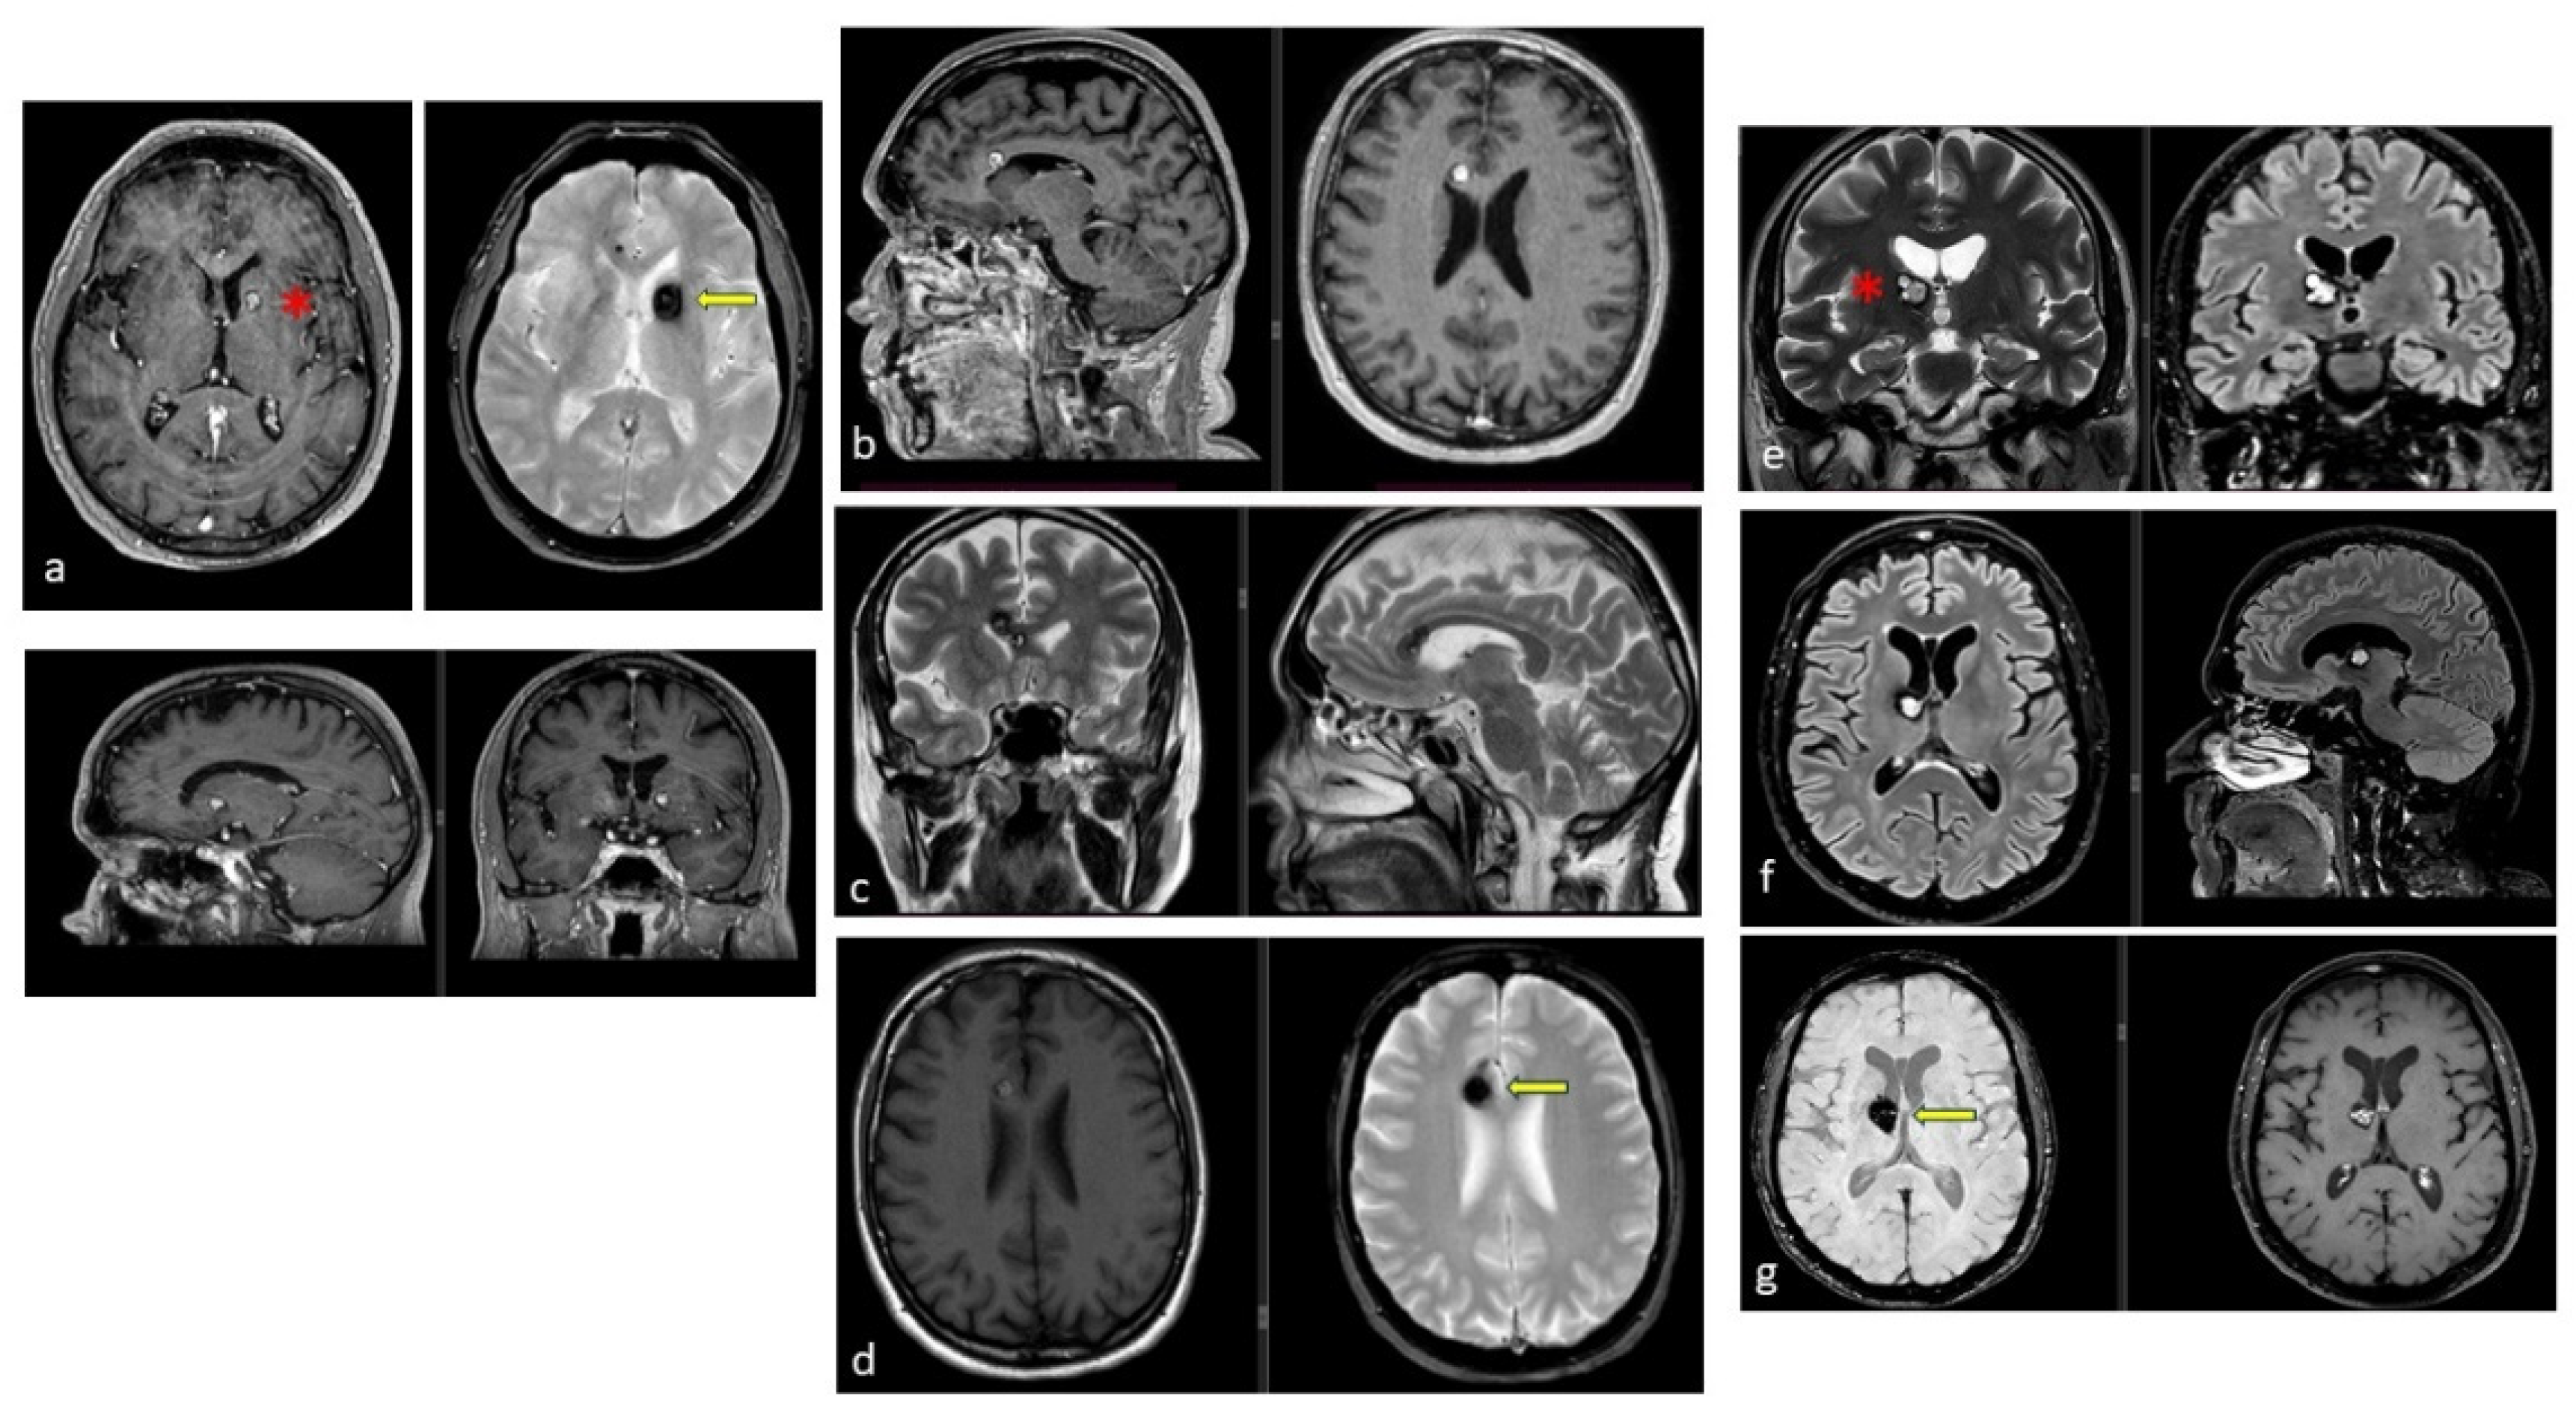

| Lesion Type | MRI Signal | Pathologic Features | Images |

|---|---|---|---|

| Type I | T1: hyperintense core T2: hyper- or hypointense core with surrounding hypointense rim | Subacute hemorrhage surrounded by a rim of hemosiderin-stained macrophages and gliotic brain | ![]() |

| Type II | T1: reticulated mixed signal core T2: reticulated mixed signal core with surrounding hypointense rim resulting in the “popcorn” appearance GE: low signal rim with blooming | Loculated area of hemorrhage and thrombosis of varying age, surrounded by gliotic, hemosiderin-stained brain; in large lesions, areas of calcification may be seen | ![]() |

| Type III | T1: iso- or hypointense T2: hypointense with a hypointense rim that magnifies the size of the lesion GE: hypointense with greater magnification than T2 | Chronic resolved hemorrhage, with hemosiderin staining within and around the lesion | ![]() |

| Type IV | T1: poorly seen or not visualized at all T2: poorly seen or not visualized at all GE: punctate hypointense lesions | Thought to be capillary telangiectasias | ![]() |